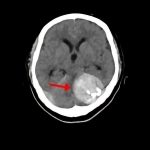

断層撮影

手術前1

手術前2